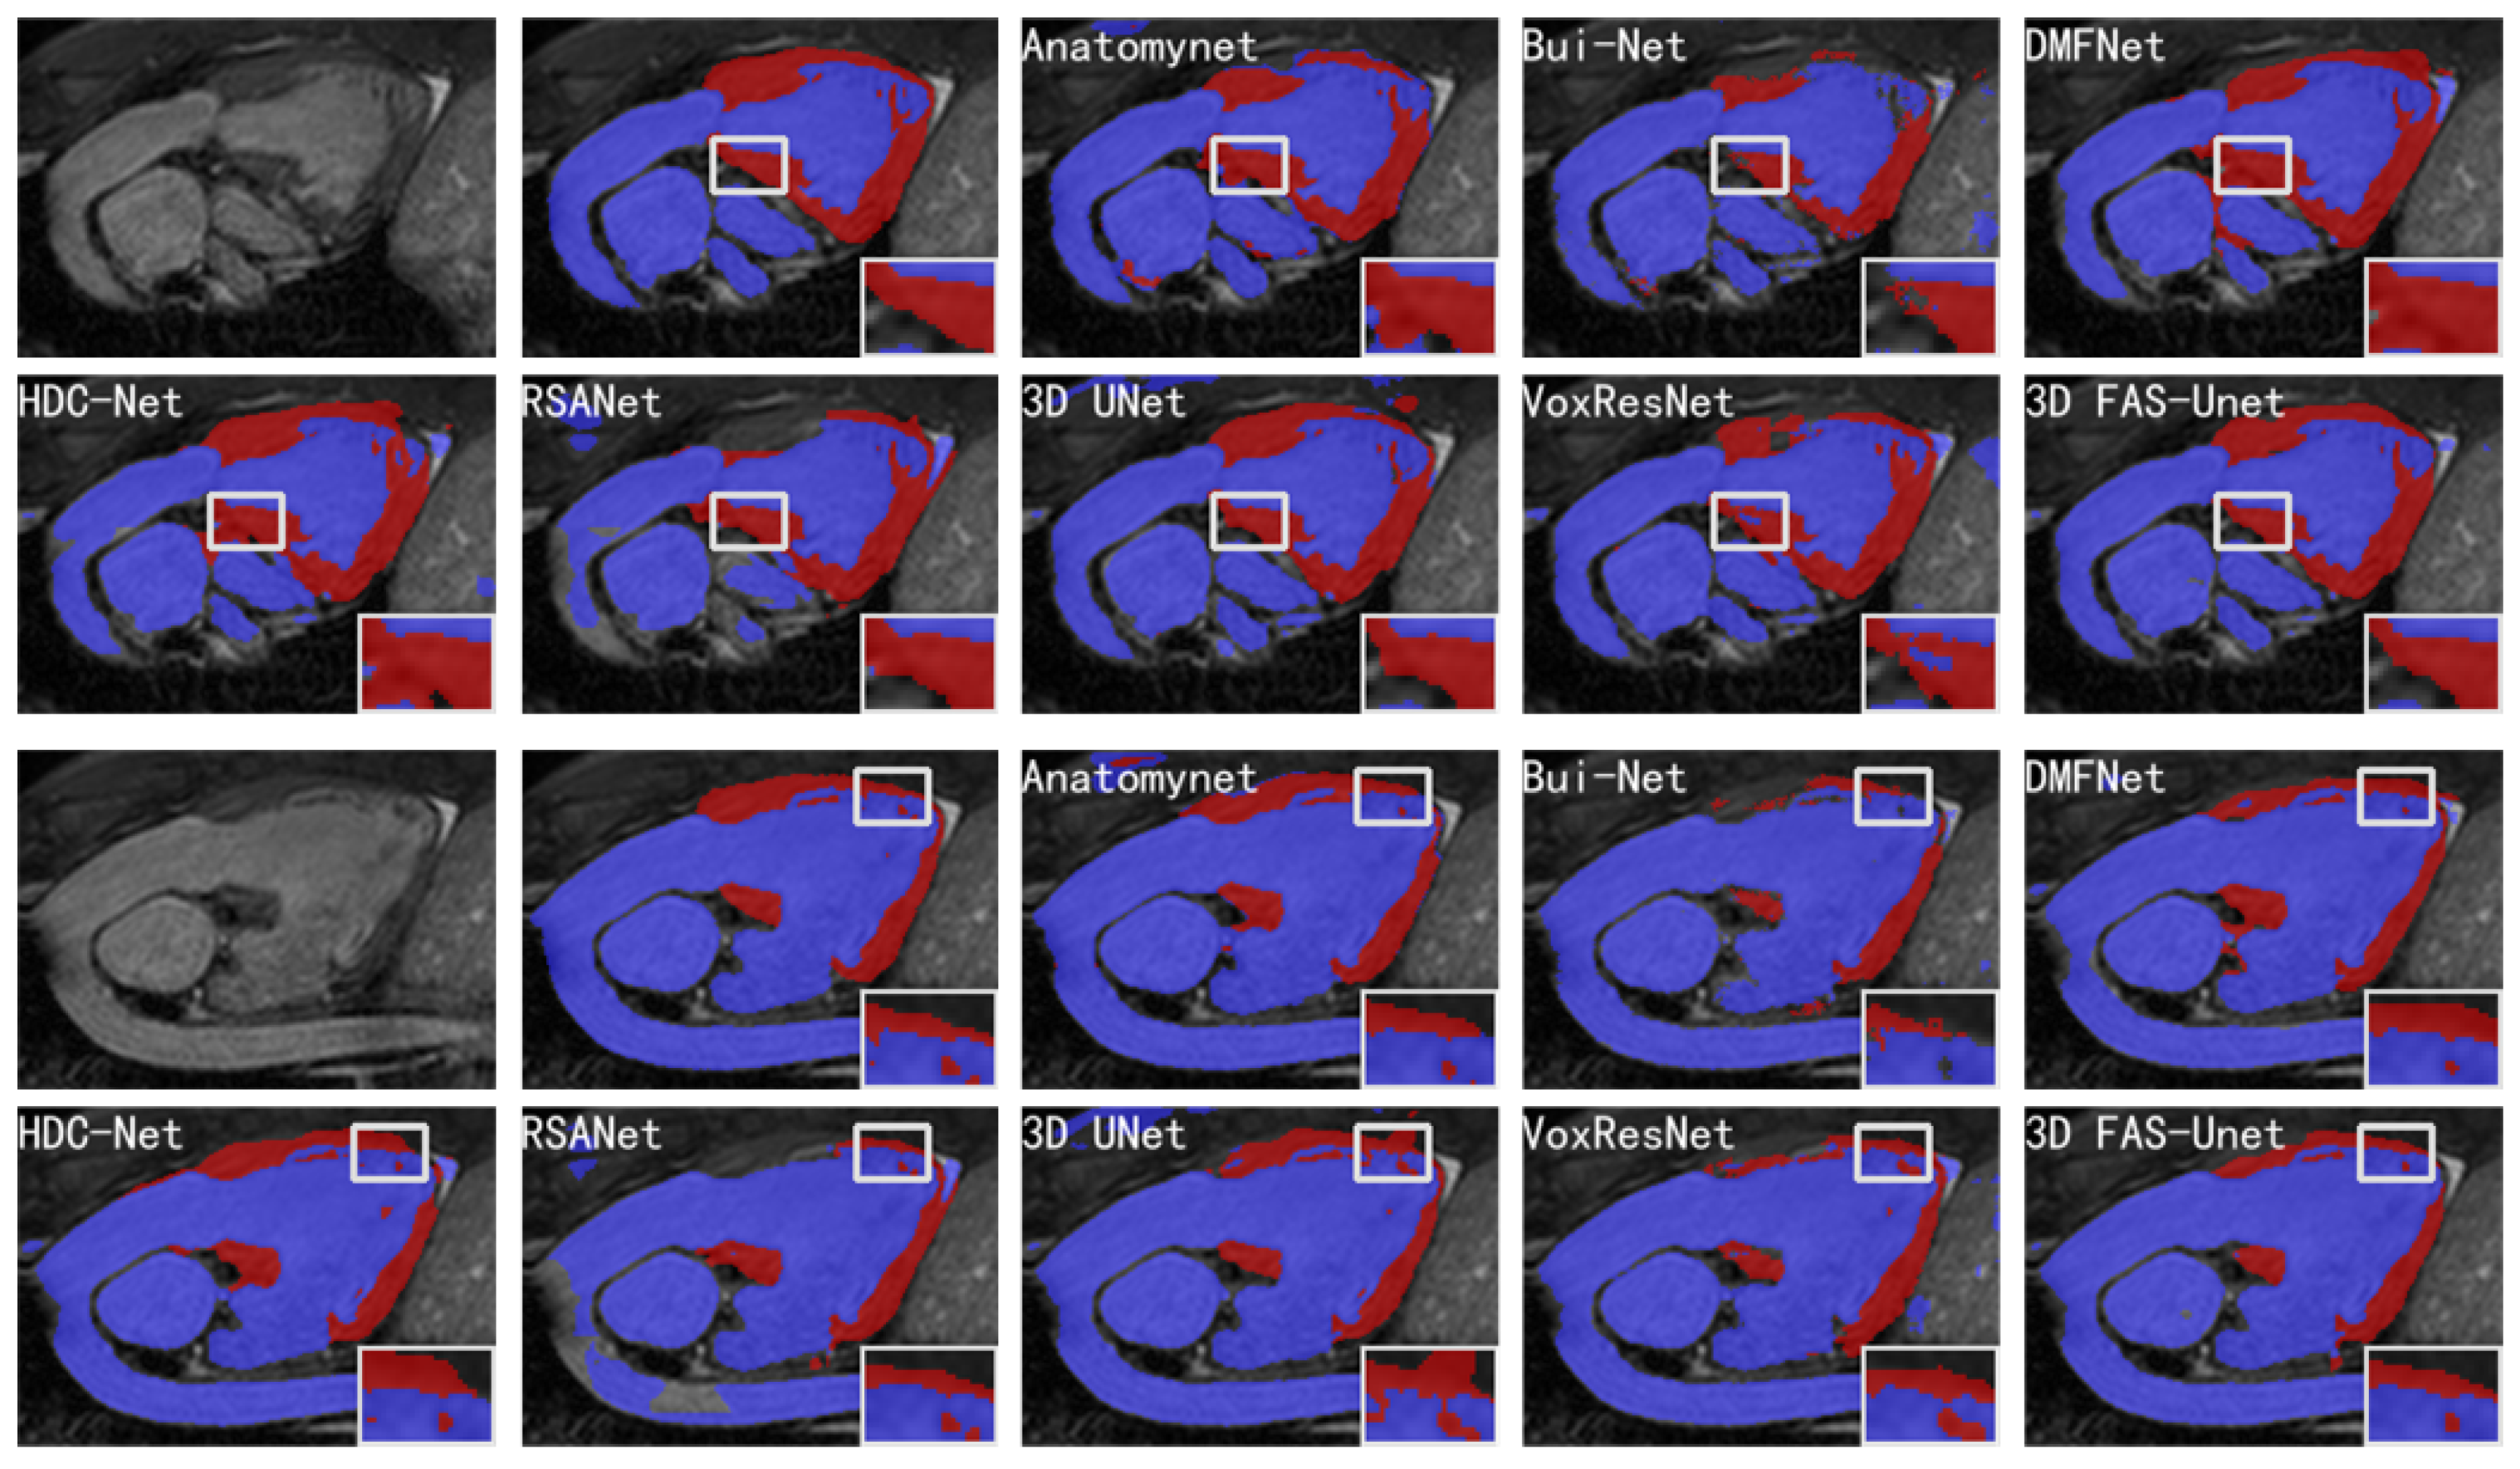

Figure 4 visualizes the segmentation results of different methods on two slices of the HVSMR-2016 datasets, and it can be clearly observed that the proposed model highlighted less over-segmented regions outside the ground-truth compared with other methods. Meanwhile, it also can show that it was hard for our method to be affected by the voxels in the background region, where it did not predict the voxels of the background region as blood pools or myocardium, but most other methods predicted more background voxels as the object. The results showed that these methods are easily affected by noise in the background region.

Figure 4.

Visualizations of different methods for cardiovascular MR segmentation of different slices. From left to right in the first and third rows: the original images, the ground-truth, and the segmentation results of AnatomyNet, Skip-connected 3D DenseNet, and DMFNet, respectively. From left to right in the second and fourth rows: the segmentation results of HDC-Net, RSANet, 3D UNet, VoxResNet, and 3D FAS-UNet, respectively. The blue and red colors represent blood pool and myocardium, respectively.

In general, one can observe that AnatomyNet, VoxResNet, and 3D UNet showed obvious segmentation noise (over-segmented region). The reason is that the network collects much noise information in the interactions from input data of the network due to a too simple data pre-processing method, which affects the feature extraction. Several methods presented over-segmentation in the myocardial zoom-in, because the pixel value of this organ is very close to the background. The myocardium is structurally distorted, which makes the shape of the myocardium completely different compared to normal/healthy myocardium. Although VoxResNet did not have this phenomenon, it divided the middle part of the myocardial region into blood pools, which was also an obvious error segmentation. Only 3D UNet and our method performed better; especially, our method was closer to the ground-truth in shape. Further, all methods had poor segmentation results in the upper myocardial region; the intensity homogeneity between this organ and the upper background indicates that this region is very difficult to segment. We can see from the zoom-in results that many methods have obvious over-segmentation or under-segmentation for the myocardium and blood pool. Compared with Bui-Net and RSANet, we observed that the proposed learnable specialized FAS-UNet network still had obvious advantages in this region, and the results were very close to the ground-truth in the myocardial region (red) with respect to the shape and size. For the blood pool region (blue), our results did not show significant differences with other methods.